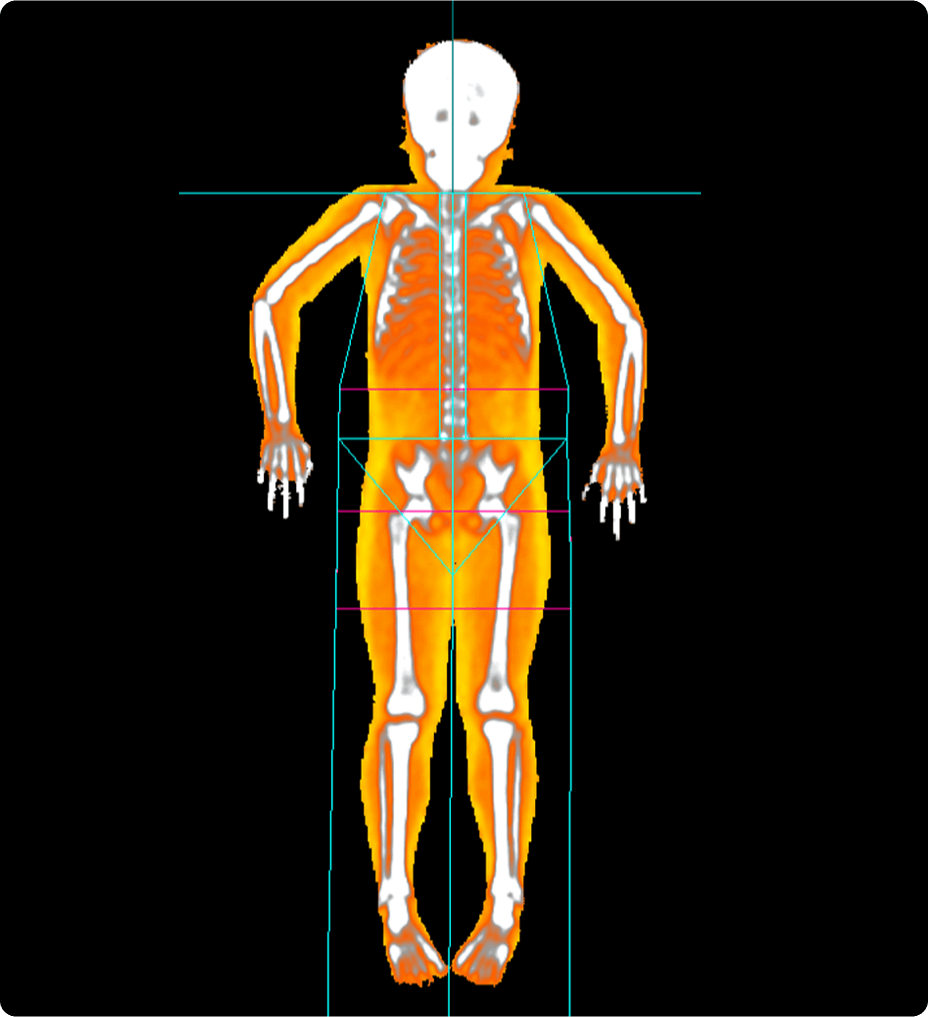

Perfusion maps and tissue classification

• Fully integrated with CT Perfusion 4D for visualization of perfusion functional maps³

• Deep Learning brain ventricle segmentation to prevent ventricular matter inclusion in quantitative results and improve visual inspection of the maps

• Automated computation of the functional maps

• Tissue Classification map segmented from absolute or relative values, customizable thresholds and user selectable input maps

• Mismatch volume and ratio calculated from the Modified Perfusion region and the Low Perfusion region